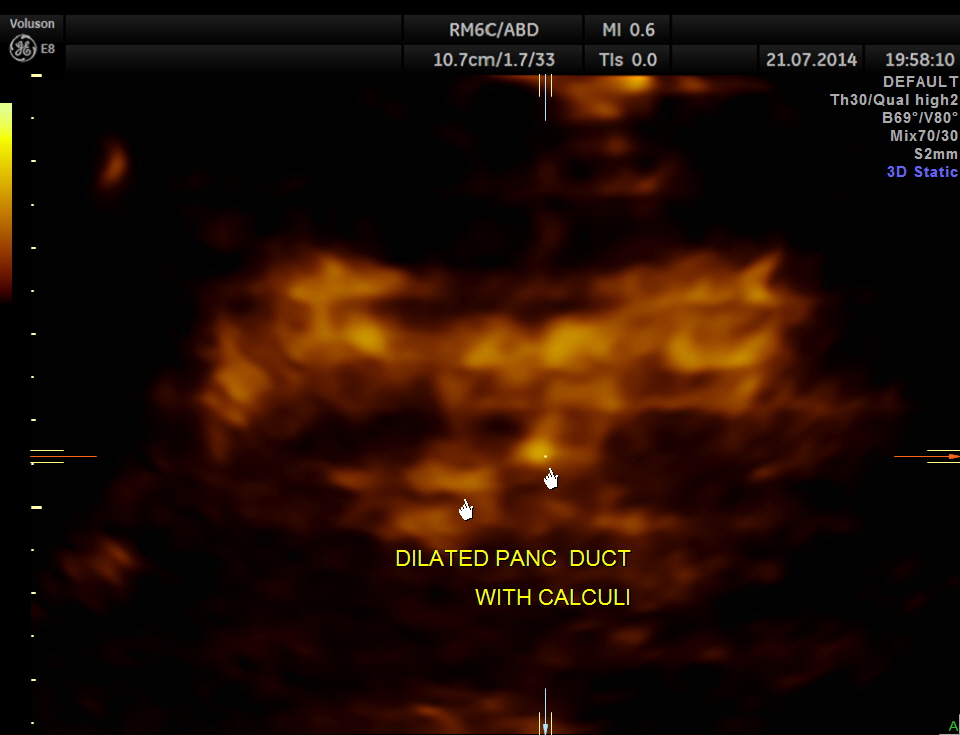

The following pictures show the pancreas.

Pancreatic duct is dilated prominently.

Pancreatic duct dilated.- 12.9 mms.

Pancreatic calculi are seen.